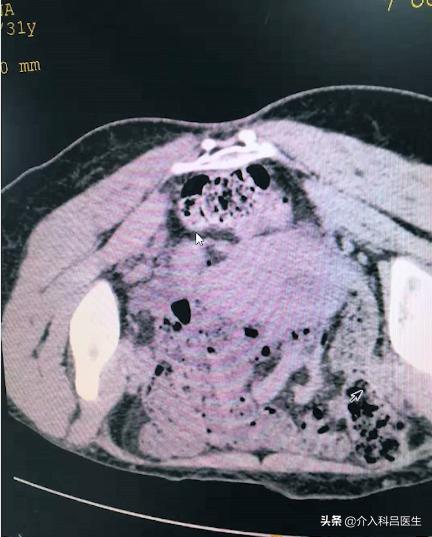

图是CT的图像,在臀部扎针进来,把里面的囊液抽出来。我没有照囊液的图片,囊液有一百多毫升,全是那种粘稠的血性的。

抽出囊液后,我们打酒精硬化。图可以看到巧克力囊肿没了,就剩这么一点了,这是超级微创的一个治疗方法。